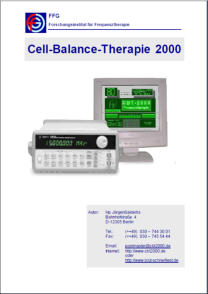

Aufhebung von Geldrollenbildung im Blut

Aufhebung von Geldrollenbildung im Blut

Aufhebung von Geldrollenbildung im Blut